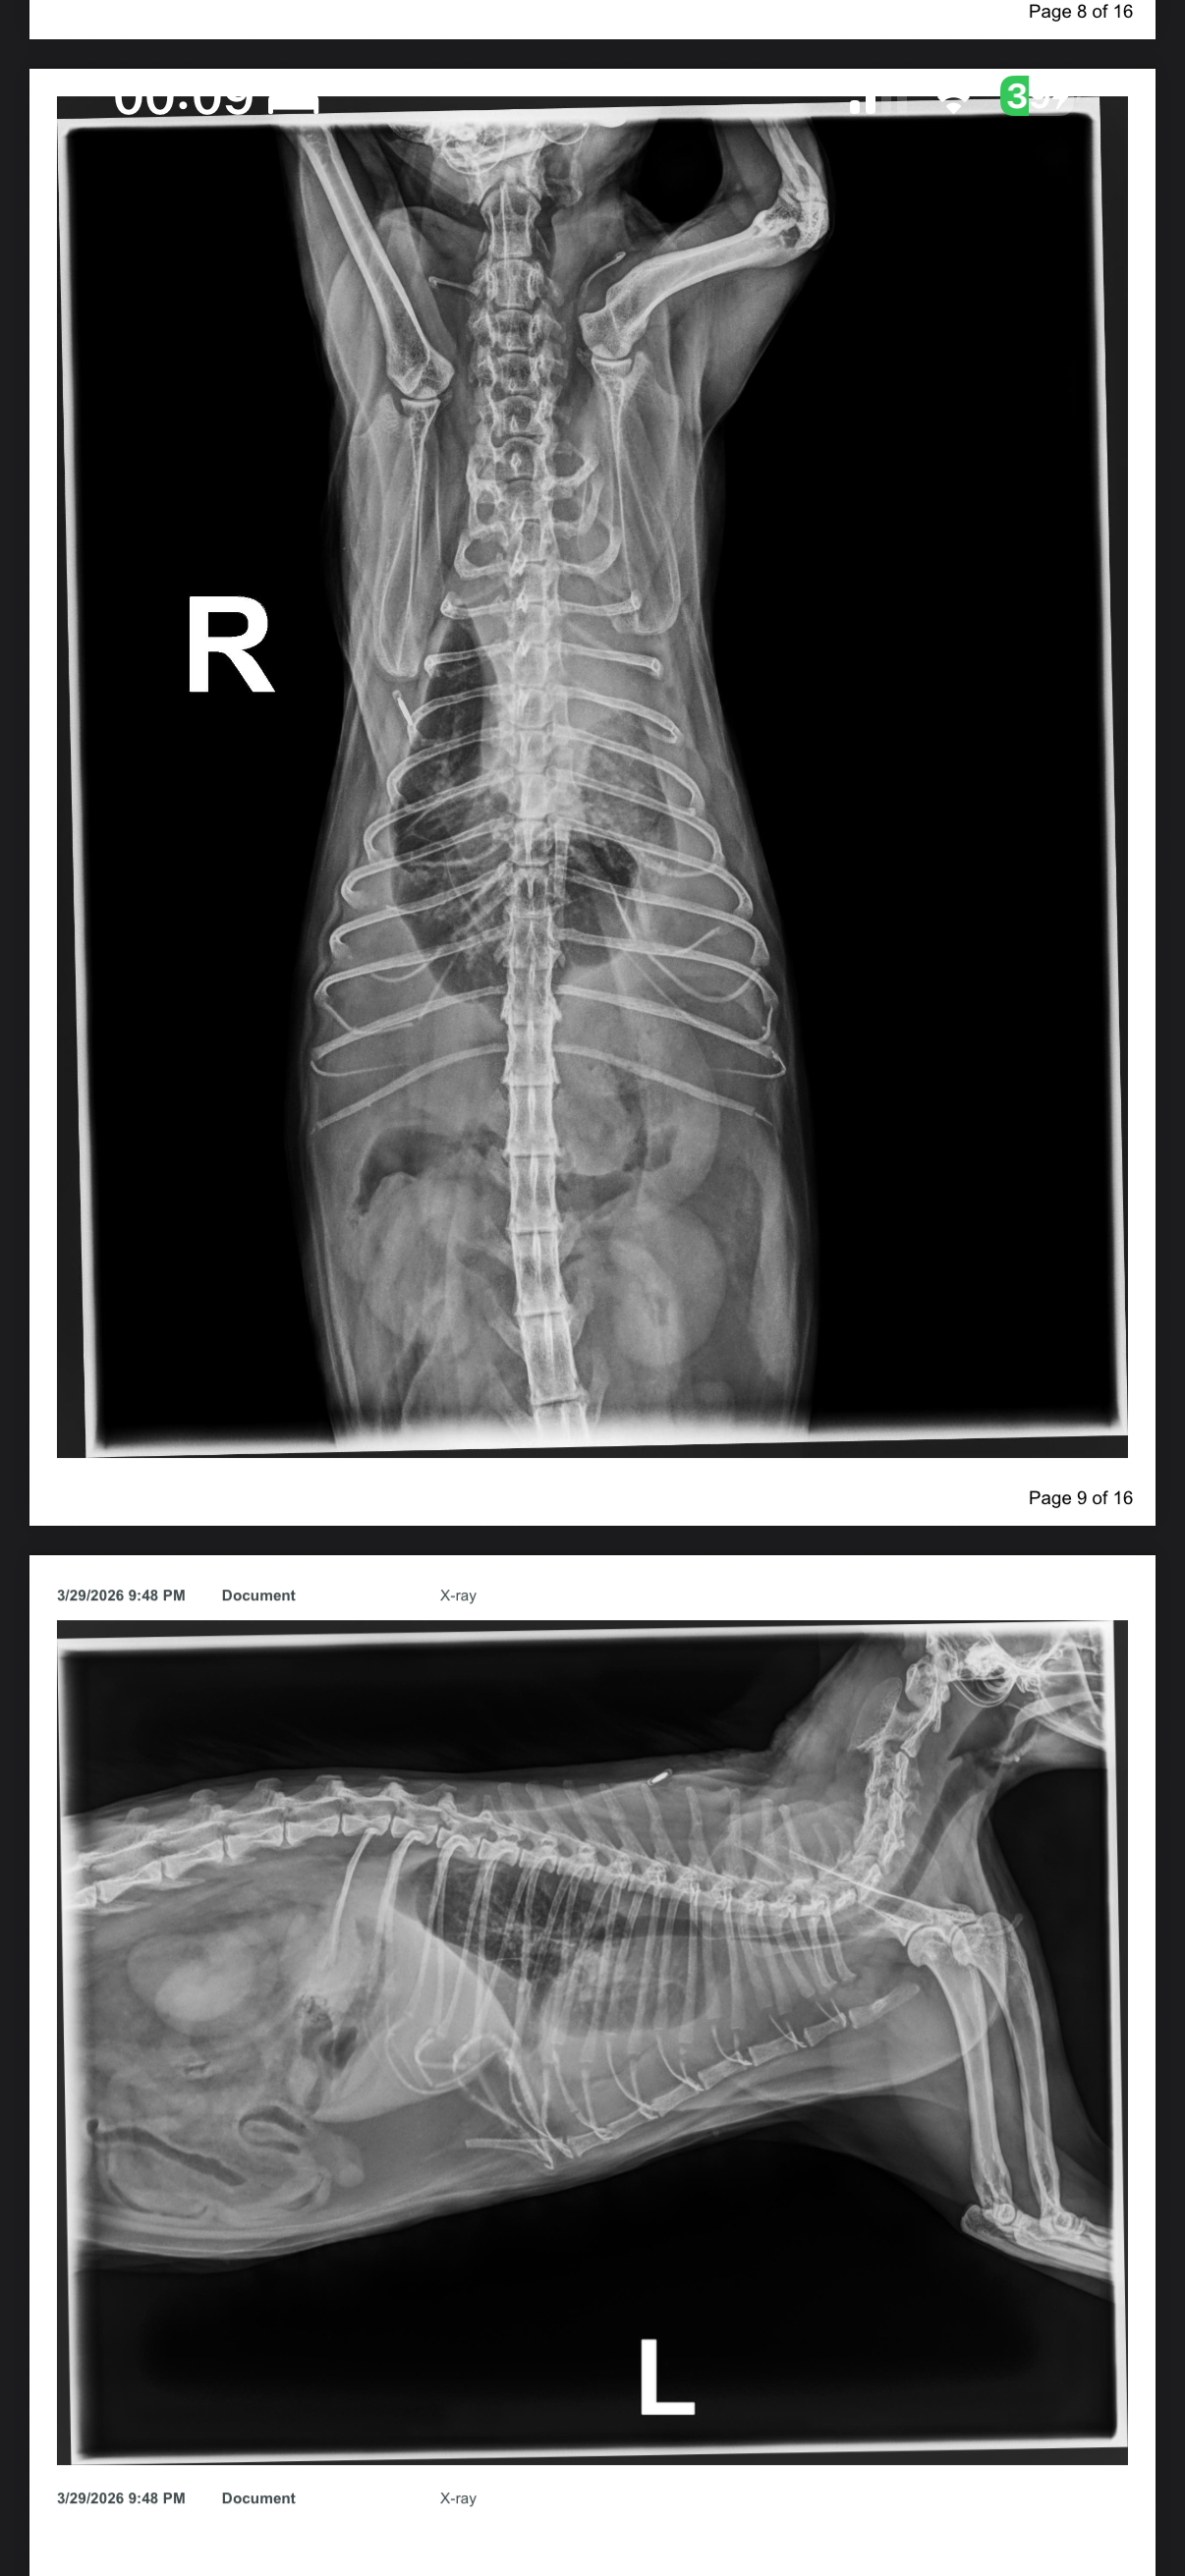

This is my cat, Cleo. She is seven years old and has been diagnosed with pleural effusion. The vet has advised that she needs emergency care as soon as possible, otherwise, euthanasia may be the only option, and I am not prepared to lose her.

The cause of her condition is still unknown at this time, but it may be due to congestive heart failure (CHF) or possibly cancer. We are still waiting for further tests to understand what she is facing.